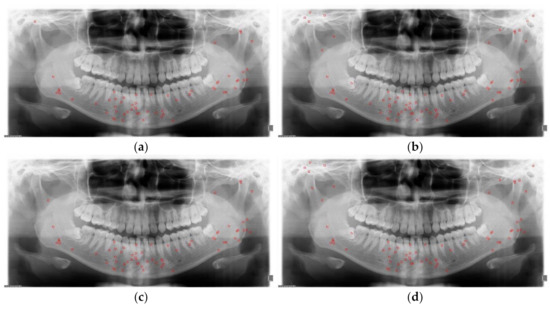

Mandibular fracture is one of the most frequent injuries in oral and maxillo-facial surgery. Radiologists diagnose mandibular fractures using panoramic radiography and cone-beam computed tomography (CBCT). Panoramic radiography is a conventional imaging modality, which is less complicated than CBCT. This paper proposes the [...] Read more.

Mandibular fracture is one of the most frequent injuries in oral and maxillo-facial surgery. Radiologists diagnose mandibular fractures using panoramic radiography and cone-beam computed tomography (CBCT). Panoramic radiography is a conventional imaging modality, which is less complicated than CBCT. This paper proposes the diagnosis method of mandibular fractures in a panoramic radiograph based on a deep learning system without the intervention of radiologists. The deep learning system used has a one-stage detection called you only look once (YOLO). To improve detection accuracy, panoramic radiographs as input images are augmented using gamma modulation, multi-bounding boxes, single-scale luminance adaptation transform, and multi-scale luminance adaptation transform methods. Our results showed better detection performance than the conventional method using YOLO-based deep learning. Hence, it will be helpful for radiologists to double-check the diagnosis of mandibular fractures. Full article

Show Figures